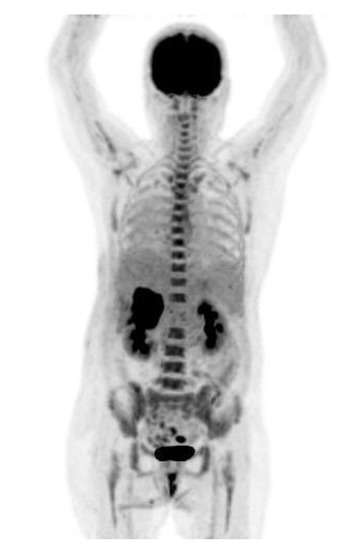

2. Case Presentation